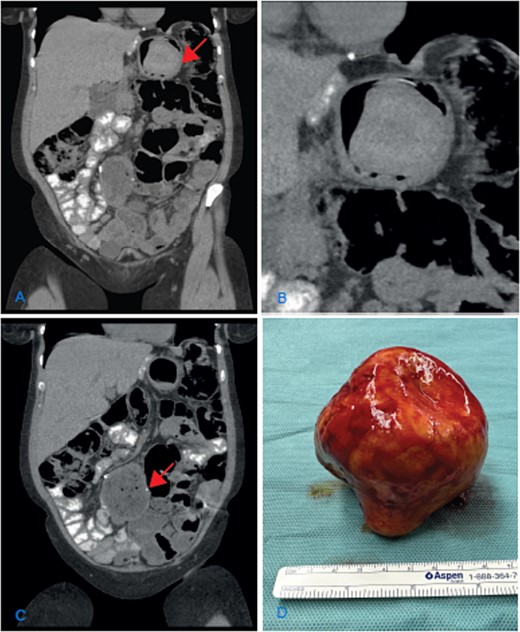

(A) Coronal CT scan image showing the dilatation of the gastric remnant with hypodensemass (arrow); (B) zoom of the gastric remnant with a 5-cm hypodense mass; (C) coronal CT scan image of the dilated JJ-anastomosis (arrow); (D) retrieved specimen a gallstone with approximately 10-cm diameter.

An elective laparotomy was performed. By palpation of the gastric remnant, a hard mass was detected. The specimen was retrieved through a gastrotomy. A hard yellow-brown stone ~10 cm in diameter was found intraluminally. After retrieving the intraluminal mass, the dilated side-to-side JJ-anastomosis was resected and reconstructed in an end-to-side fashion.

The chemical analysis confirmed the macroscopic suspicion of a cholesterol gallstone (Fig. 1D). The follow-up was uneventful, and the symptoms resolved.